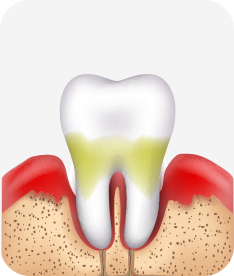

치주염 (중기~말기)

주기적으로 잇몸이 붓고 피가 나며, 욱씬하거나 우리한 통증이 나타남.

치주치료 및 정도에 따라 치주수술(잇몸수술)이 필요함. 향후 관리 정도에 따라 3~6개월 간격으로 내원하여 유지치료를 시행하여야 함.

치주염 (말기)

잇몸이 항상 부어 있으며, 이가

흔들리는 정도가 점점 심해짐.

치주치료가 필요하며, 정도에 따라 치아를 발치하여야 할 수 있음.